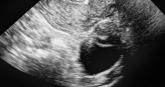

Can US “pattern recognition” of classic adnexal lesions reduce surgery, and even referrals for other imaging, in average-risk women?